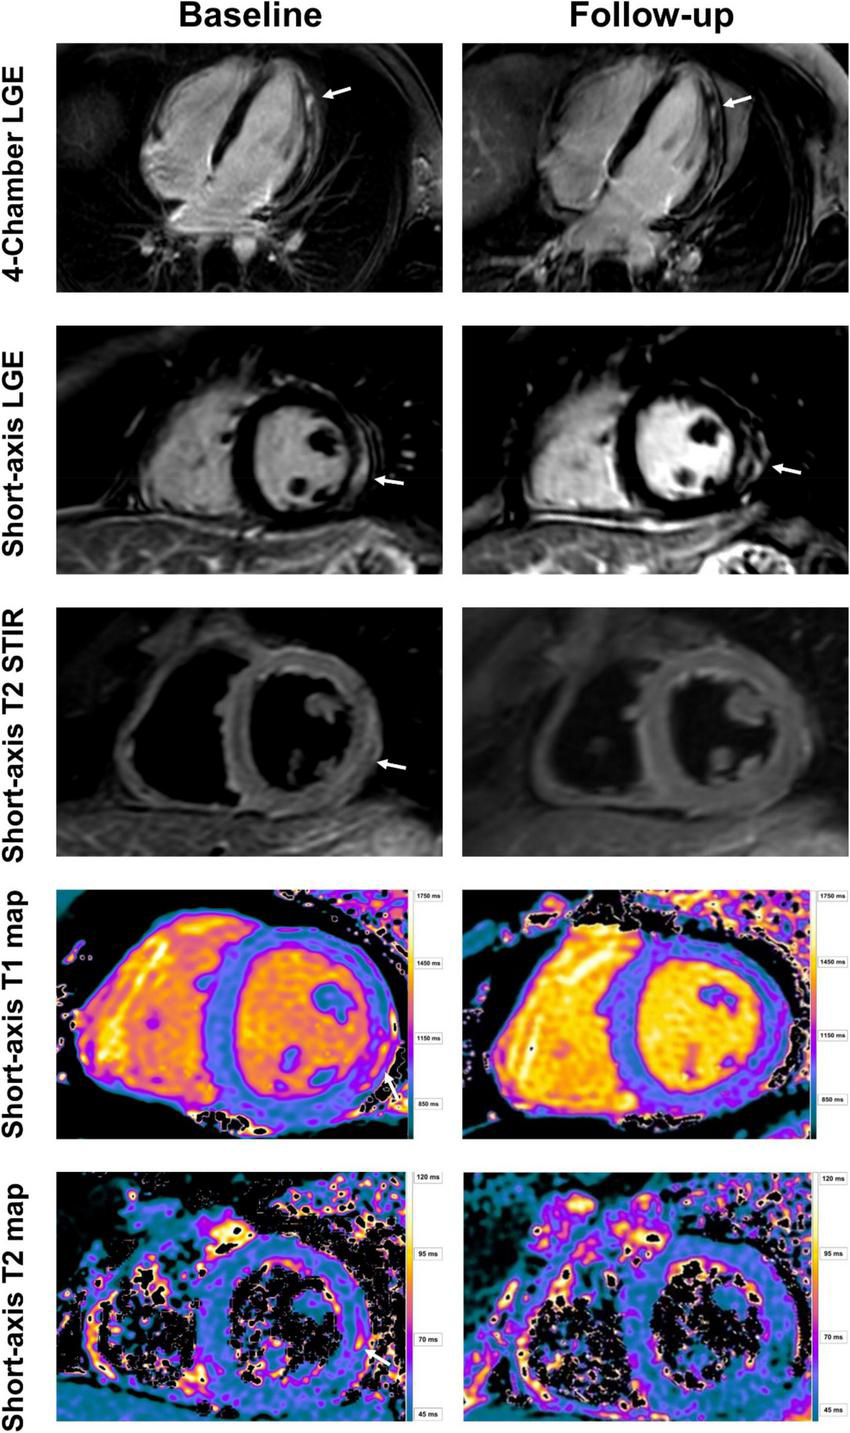

FIGURE 2

Baseline and follow-up cardiac imaging in a 25-year-old male with acute vaccine associated myocarditis after receiving his second vaccine with Pfizer/BioNTech. Short-axis and 4-chamber late gadolinium enhancement (LGE) views demonstrate subepicardial enhancement along the midventricular and apical inferolateral wall (arrows). T2 short-axis short tau inversion recovery (STIR) imaging corresponding to the LGE findings shows a resolution of edema from baseline to follow-up (arrow). Normalization of T1 and T2 relaxation times are also demonstrated over time (arrow). Note, however, the persistent LGE along the inferolateral wall even at follow-up, consistent with scar tissue.